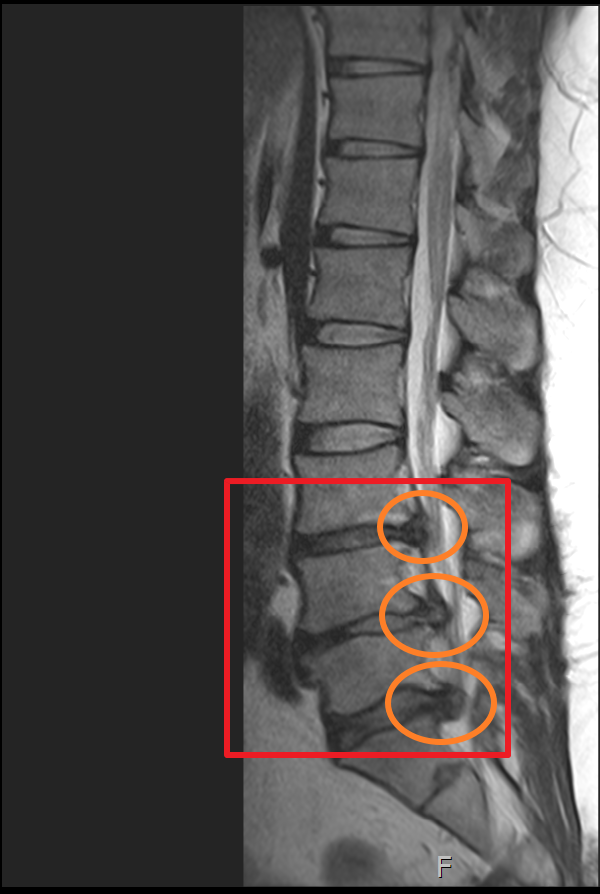

마지막 허리디스크 MRI는 2020년에 촬영했습니다. 마찬가지로 사진을 보시면 최초 발병한 허리디스크 첫 번째 동그라미는 흡수가 된 게 눈에 보일 정도였으나 4년뒤엔 두 번째 동그라미와 세 번째 동그라미 디스크가 많이 튀어나와 신경을 누르고 있는 게 보입니다.

하지만 MRI 상 표시된 부분을 보면 첫 번째 허리디스크가 튀어나왔던 부분이 흡수된 게 확실히 보이며 이제는 다른 부분에 허리디스크가 눌려 신경을 누르고 있는 게 보입니다.

마지막으로 제가 촬영했었던 MRI 촬영 이미지를 첨부해 볼까 합니다. 이미지 순서대로 2014년, 2018년, 2020년 촬영했던 MRI 사진입니다. MRI 촬영 당시 허리디스크 상태가 좋지 않은 상황에서만 세 차례 찍었던 것이기에 이점도 고려해서 참고하시면 좋을 듯합니다.

이미지를 보시면 빨간색 네모 칸에 하얀색 기다란 세로 라인이 신경이 지나가는 부분이며 가장 바깥쪽 두꺼운 흰색 부분은 배 쪽의 지방입니다.

2020년 첫번째, 두번째 터졌던 허리디스크가 많이 흡수되어 신경을 누르고 있는 디스크 압박이 많이 좋아졌으나 세번째 허리디스크가 터진 곳이 심해진 상황.